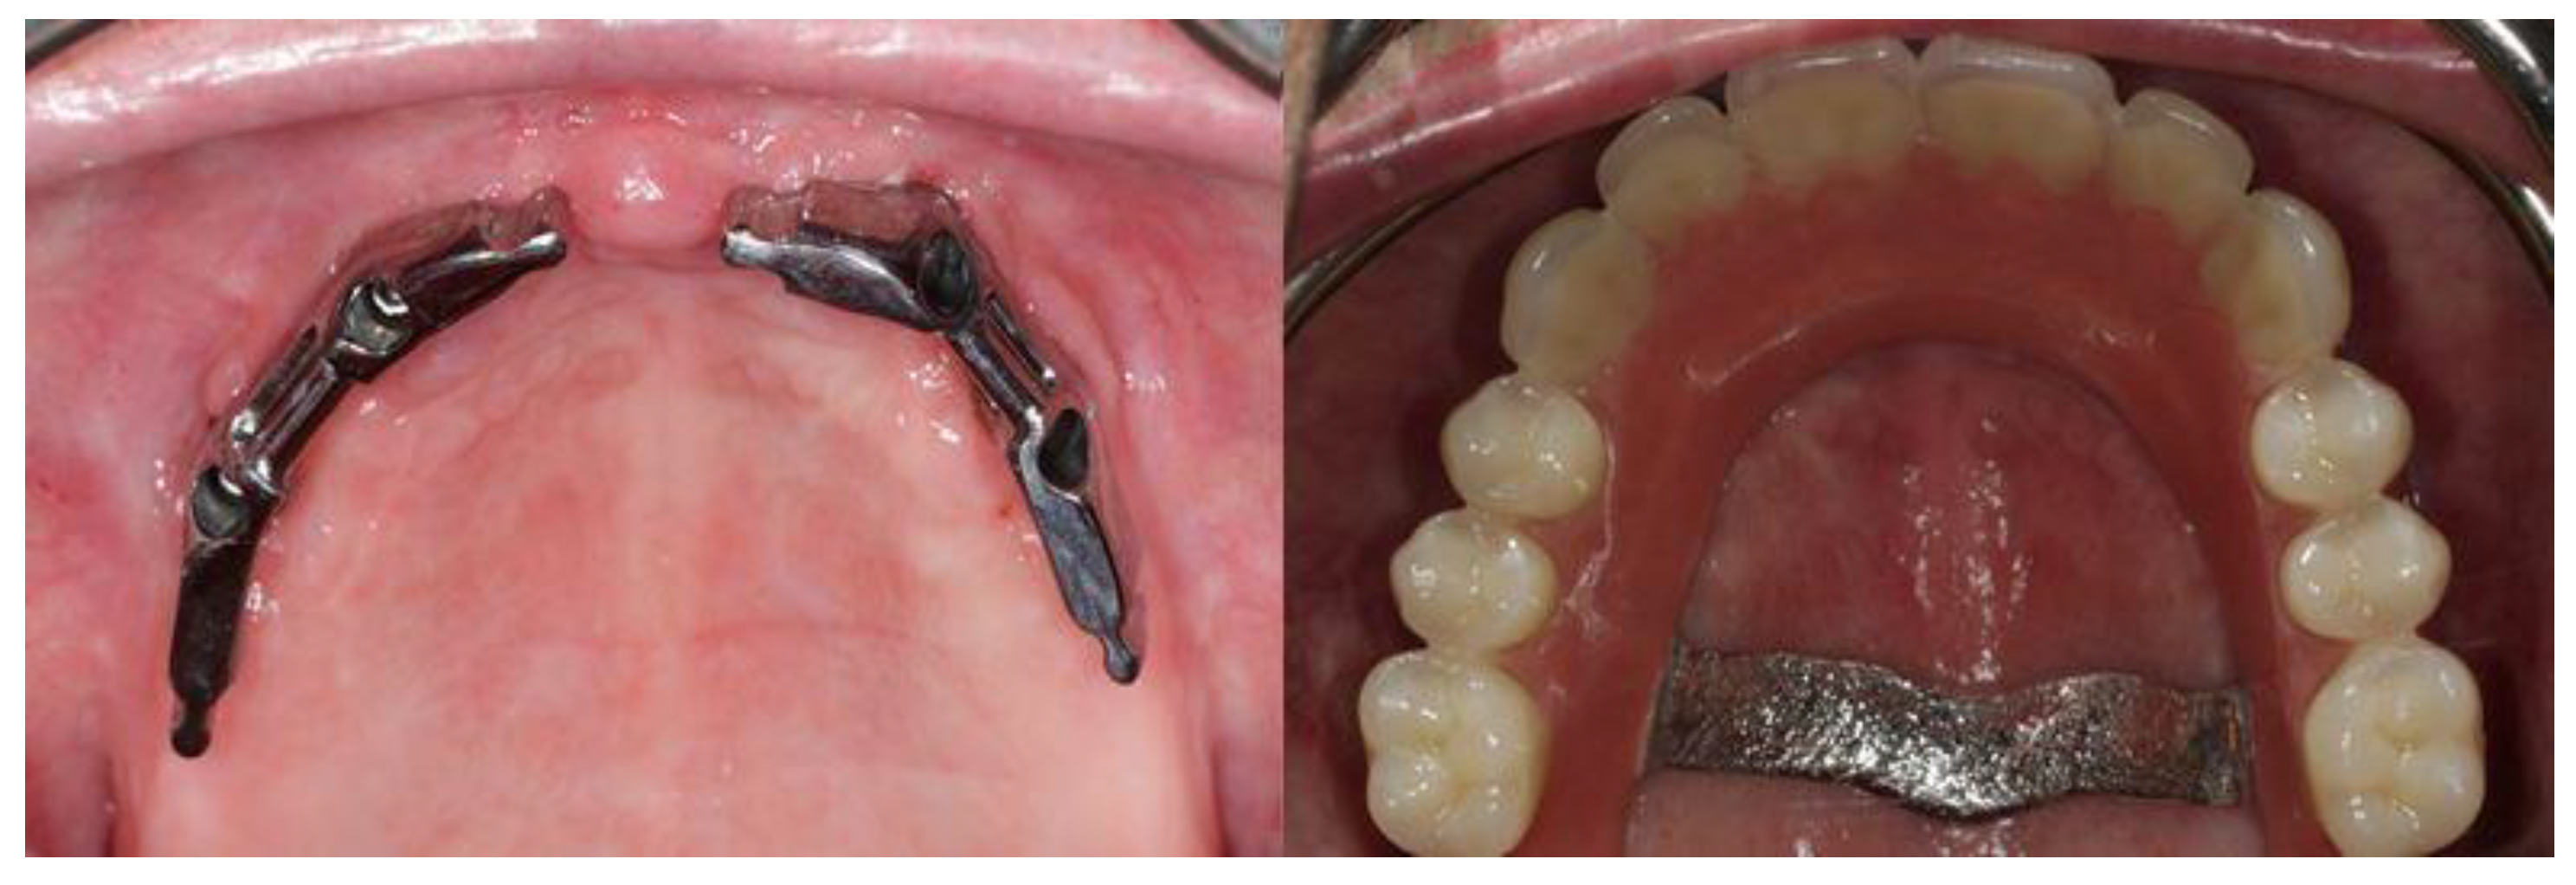

2. Case Report